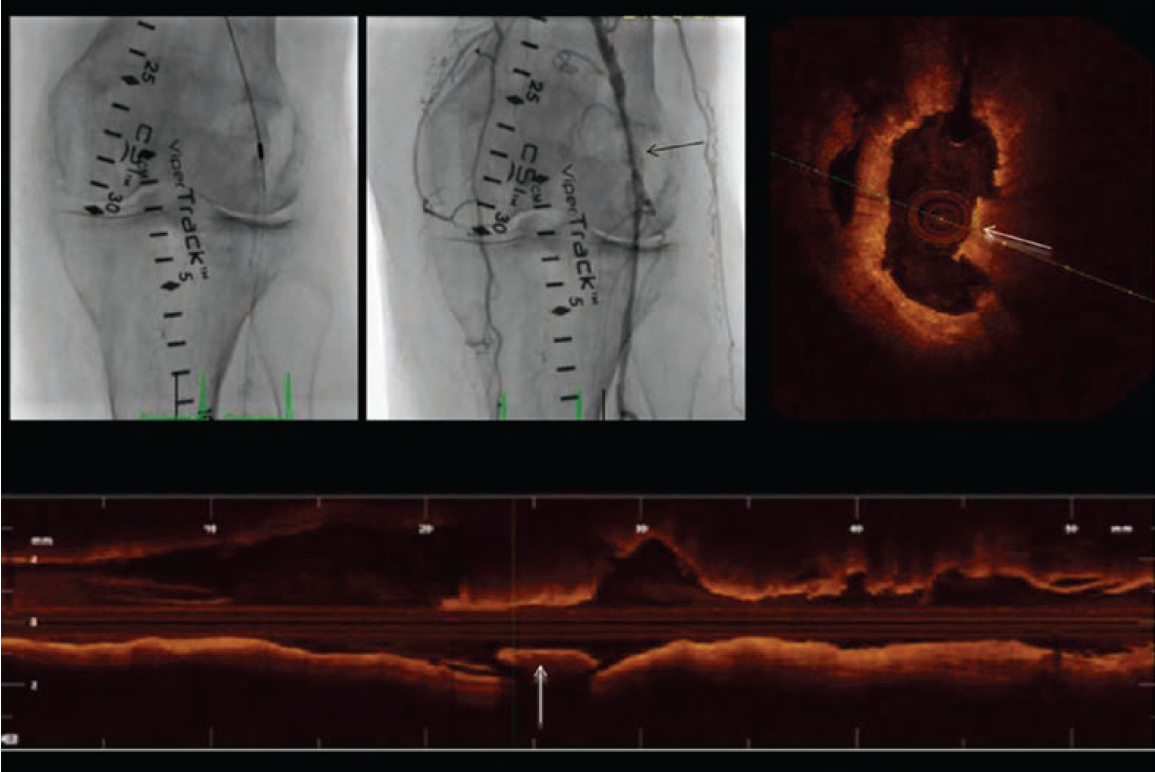

Case 3: Orbital Atherectomy and OCT-Guided Percutaneous Transluminal Angioplasty for Popliteal CTO

A 67-year-old gentleman with right lower extremity lifestyle-limiting claudication and abnormal ABI was referred to our institution for a right leg arterial angiogram and possible endovascular intervention. A 5 Fr sheath was placed in the left common femoral artery. A 5 Fr tennis racquet catheter was used for the abdominal aortogram and a 5 Fr internal

mammary (IM) catheter for the selective right femoral angiogram after left-to-right crossover. A chronic, subtotally occluded right distal popliteal stenosis extending to the tibioperoneal trunk was identified and we elected to go ahead with a endovascular recanalization approach. The 5 Fr sheath was exchanged for a 6 Fr, 45 cm long sheath. A 300 cm, .014-inch Regalia guidewire (Asahi Intecc) was advanced to the right posterior tibial artery and a baseline OCT was performed (Figure 6). Due to significant calcification identified with OCT, we decided to perform an

orbital atherectomy recanalization using the Diamondback 360 atherectomy device (Cardiovascular Systems, Inc.) in the affected segment. Although atherectomy established excellent angiographic flow, due to mild angiographic “haziness” at the site of intervention, we elected to perform a follow-up OCT (Figure 7). OCT demonstrated multiple segments of endothelial protrusion in the arterial lumen. Although data regarding the clinical significance of such OCT findings is currently absent, we decided to proceed with a 3.5 mm × 100 mm × 150 mm Sterling balloon (Boston Scientific) angioplasty. Final angiographic and OCT imaging showed good results (Figure 8).

angioplasty, with a good final result.